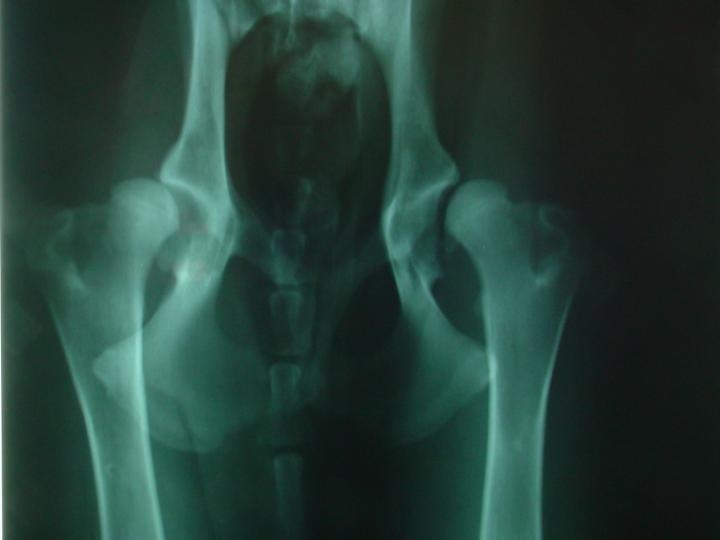

Rx: Em primeiro lugar fizemos uma sedação profunda do paciente sem a qual é impossÃvel obter um Rx com as caracterÃsticas exigidas para fazer um estudo exaustivo da displasia.

Após a sedação o paciente é colocado na mesa numa posição simétrica e paralela. No enquadramento do chasis temos que ter as asas do ilium, os buracos obturadores, ambas as rótulas no centro das trócleas e os fémures paralelos. Obtido o Rx fizemos a medição dos ∢s. O ∢ de Norberg-Obsson < 90º.